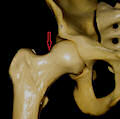

Kalça eklemi, uyluk kemiği (femur) ve leğen kemiği (pelvis) arasında bulunan, vücudun en büyük ağırlık taşıyan eklemlerinden biridir. Bu eklem, femur başının (top) ve pelvik asetabulumun (yuva) oluşturduğu bir top ve soket tipi eklemidir. Kalça eklemi 3 düzlemde hareket kabiliyeti olan bir eklemdir...